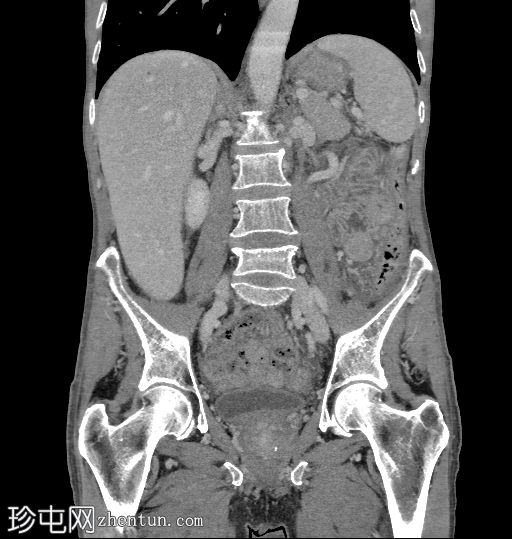

冠状位

冠状位增强扫描

5.jpg

门静脉期

6.jpg

盲肠内壁可见多条明显的血管通道,并可见局灶性强化。

动脉期可见一条早期充盈的静脉。静脉期可更清晰地显示扩张的引流静脉。未见活动性出血。